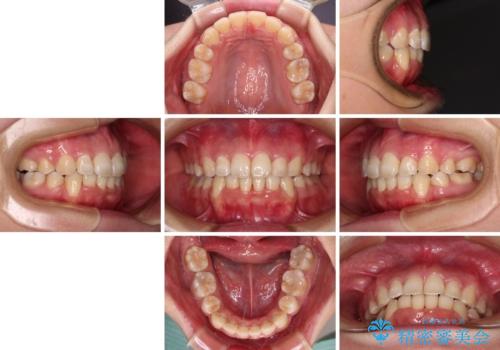

4本の歯を抜歯したことで、飛び出していた口元が引っ込み、横顔が大きく改善されました。

咬み合わせが悪化することのないようにスペースを閉じていくことができ、比較的スムーズに治療を進めることができました。